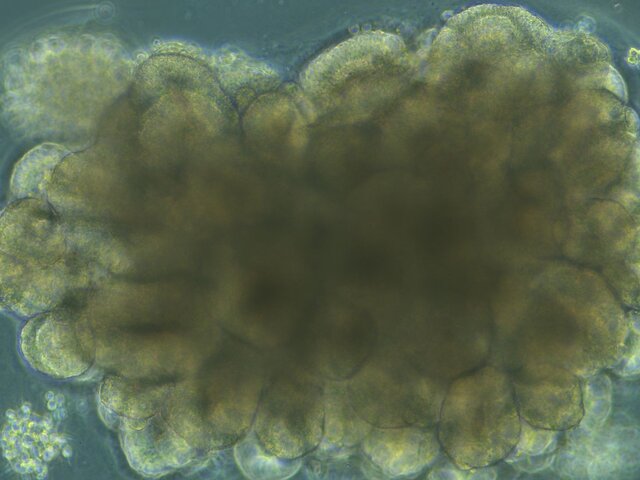

ارگانوئیدها ساختارهای سه بعدی هستند که در شرایط آزمایشگاهی کشت

میشوند و ساختار، ترکیب سلولی و عملکرد اندامها یا بافتهای خاص را

شبیهسازی میکنند. آنها از سلولهای بنیادی یا سلولهای پیشساز خاص بافت

ایجاد میشوند.

برخلاف کشتهای سلولی دو بُعدی سنتی، ارگانوئیدها تصویر دقیقتری از

اندامها و سیستمها ارائه میدهند. این به محققان اجازه میدهد تا تعاملات

پیچیده بین انواع مختلف سلول را مطالعه کنند، شرایط بیماری را شبیهسازی

کنند و درمانهای بالقوه را در یک محیط آزمایشگاهی کنترل شده آزمایش کنند.